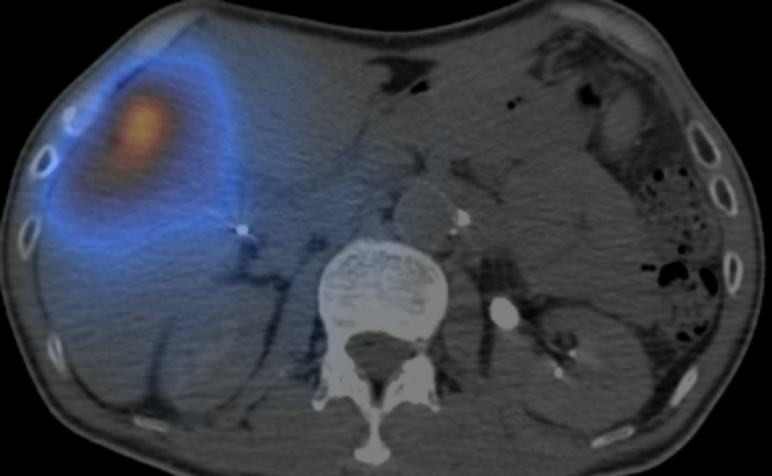

经肝动脉化疗栓塞(cTACE)是无法手术治疗的原发性肝癌常用的局部治疗方式,但对于部分复杂病灶疗效不佳。钇[90Y]树脂微球作为前沿放射性核素治疗产品,具有独特优势,其搭载的钇[90Y]能辐射高能量纯β射线,半衰期适中(64.1h)且组织穿透距离短(组织内平均射程R=2.5mm,最大射程R0=11mm),可在有效杀伤肿瘤细胞的同时最大程度保护正常肝组织。利用肝癌细胞与正常肝细胞血供来源的差异,20-60μm粒径的树脂微球可通过肝动脉精准进入肿瘤供血动脉并富集于末梢血管,实现对肿瘤的选择性体内放射治疗(SIRT),精准“狙击”病灶。本品已在我国上市,批准用于经标准治疗失败的不可切除的结直肠癌肝转移患者。2025年7月,基于DOORwaY90临床试验的数据,美国FDA提前批准钇[90Y]树脂微球用于治疗不可切除肝细胞癌。研究显示其治疗原发性肝癌的客观缓解率为98.5%。多家主流专业指南,包括CSCO、NCCN及ESMO等均推荐钇[90Y]树脂微球用于不可切除的HCC治疗。

钇[90Y]手术开始前,临床试验机构办公室牵头组织召开“钇[90Y]微球注射液使用全流程”专项培训,涵盖研究团队、介入治疗、核医学、护理团队等相关医护人员,系统强化操作规范与安全防护意识。术前评估阶段,通过99mTc-MAA后SPECT-CT检查(即Mapping)精准测算肿瘤靶区与正常肝组织血流分布,汇集包括项目组专家团队在内的多学科会诊意见,为患者量身制定个体化给药方案;手术过程中,介入科精准手术,项目组专家团队在线实时指导,核医学科对辐射剂量进行实时动态监测,临床试验机构办公室全程驻场实施质量监督,确保每一步操作均符合研究方案与临床安全规范,实现治疗精准性与患者安全性双重保障。